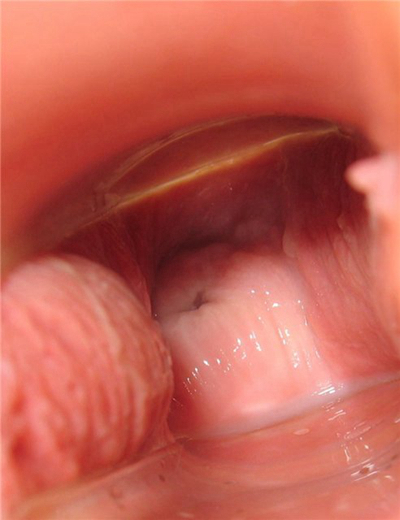

子宮肥大圖片

子宮肥大圖 (9)